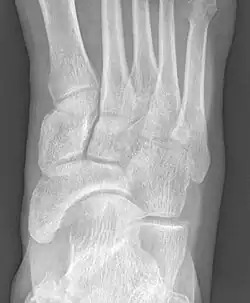

-

From left to right: Type 1, 2 and 3 -